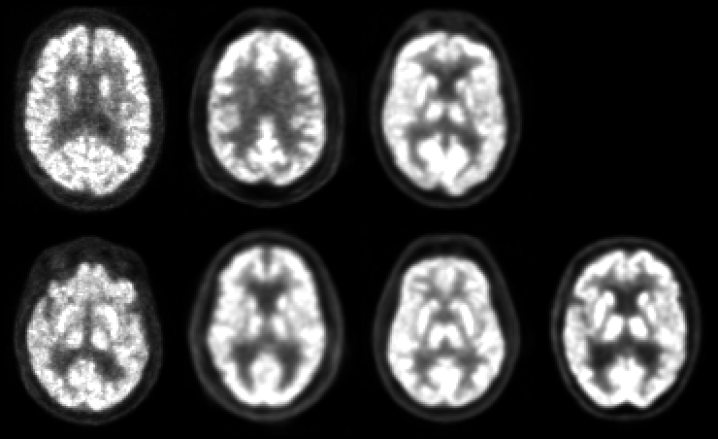

Having addressed the information preference problem, we can resume our analysis of the latent generative model to derive meaningful representations of our subjects. We feed our database to the VAE model, obtain the latent representation of neuroimaging for the neurodegenerative disease we are working with, and finally decode and plot curves of loss to see the performance of our model. But, to our surprise, when we take a look at our reconstructed images or volumes we find the following image (2).

After all the issues we have already dealt with and solved, something has gone wrong again. But, what exactly happened? We are encountering a common issue in deep learning: our model appears to be trapped in a local minimum of the loss function. The loss function is a non-linear multi-variate function that lives in a space of large dimensionality. Its structure is highly complex and it has many local minima [36, 37, 38]. Among those minima, there is one local attractor, which is the mean of the distribution. In the ELBO, one simple solution for qϕ(z|x)q_{\phi}(z|x) to be close to the prior p(z)p(z) is simply to approximate μ(x)\mu(x) to 0 and σ(x)\sigma(x) to 11, since the prior is a normal distribution. This is catastrophic, because in this case we are not capturing the variability. Instead, what our model is doing is compute and decode an average brain of the subjects of the database, paying no attention to the inter-subject variability. This is exactly what we are seeing in the figure (2).

Refer to caption

Figure 2: On top: Input volume slices from the neuroimaging database. On bottom: reconstructed images from random subjects using a variational autoencoder using the volumes on top as input. In the figure we see that the reconstruction of each subject is the same. This happens because the model is stuck at the mean local minimum, and thus it is not able to capture the inter-subject variability.